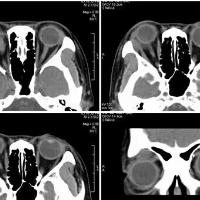

女,54岁,头痛头晕月余,无眼部症状及视力异常。 影像表现:右侧眼球后方占位病变,考虑海绵状血管瘤可能性大,鉴别:视神经鞘瘤、脑膜瘤及炎性假瘤。 病例点评:眼眶内血管瘤是较常见的良性肿瘤,其中以海绵状血管瘤最常见。可发生于任何年龄,主要表现为眼球突出及偏位,在低头或哭泣时可有突眼加重。可经眶缘触及具有压缩性的肿块。视力损害多较缓慢。肿块大多位于肌锥内,其次为肌锥外,平扫呈边界清楚的圆形、卵圆形或分叶状肿块,增强扫描呈缓慢进行性显著强化为其特征性表现。